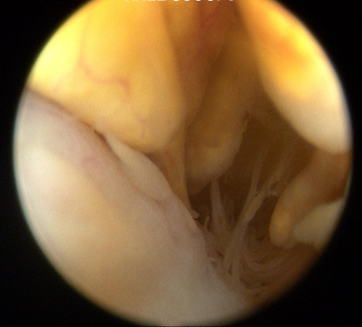

A diagnostic knee arthroscopy and biopsy was performed. This is the arthroscopic view during arthroscopy.

Q. What is your diagnosis?

Diagnosis: Pigmented villonodular synovitis

Pigmented villonodular synovitis (PVNS) is a rare benign proliferative condition affecting synovial membranes of joints, bursae or tendons, resulting from possibly neoplastic synovial proliferation with villous and nodular projections and haemosiderin deposition. PVNS is most commonly mono articular (80% knee joint) but occasionally it can be oligo articular [1].